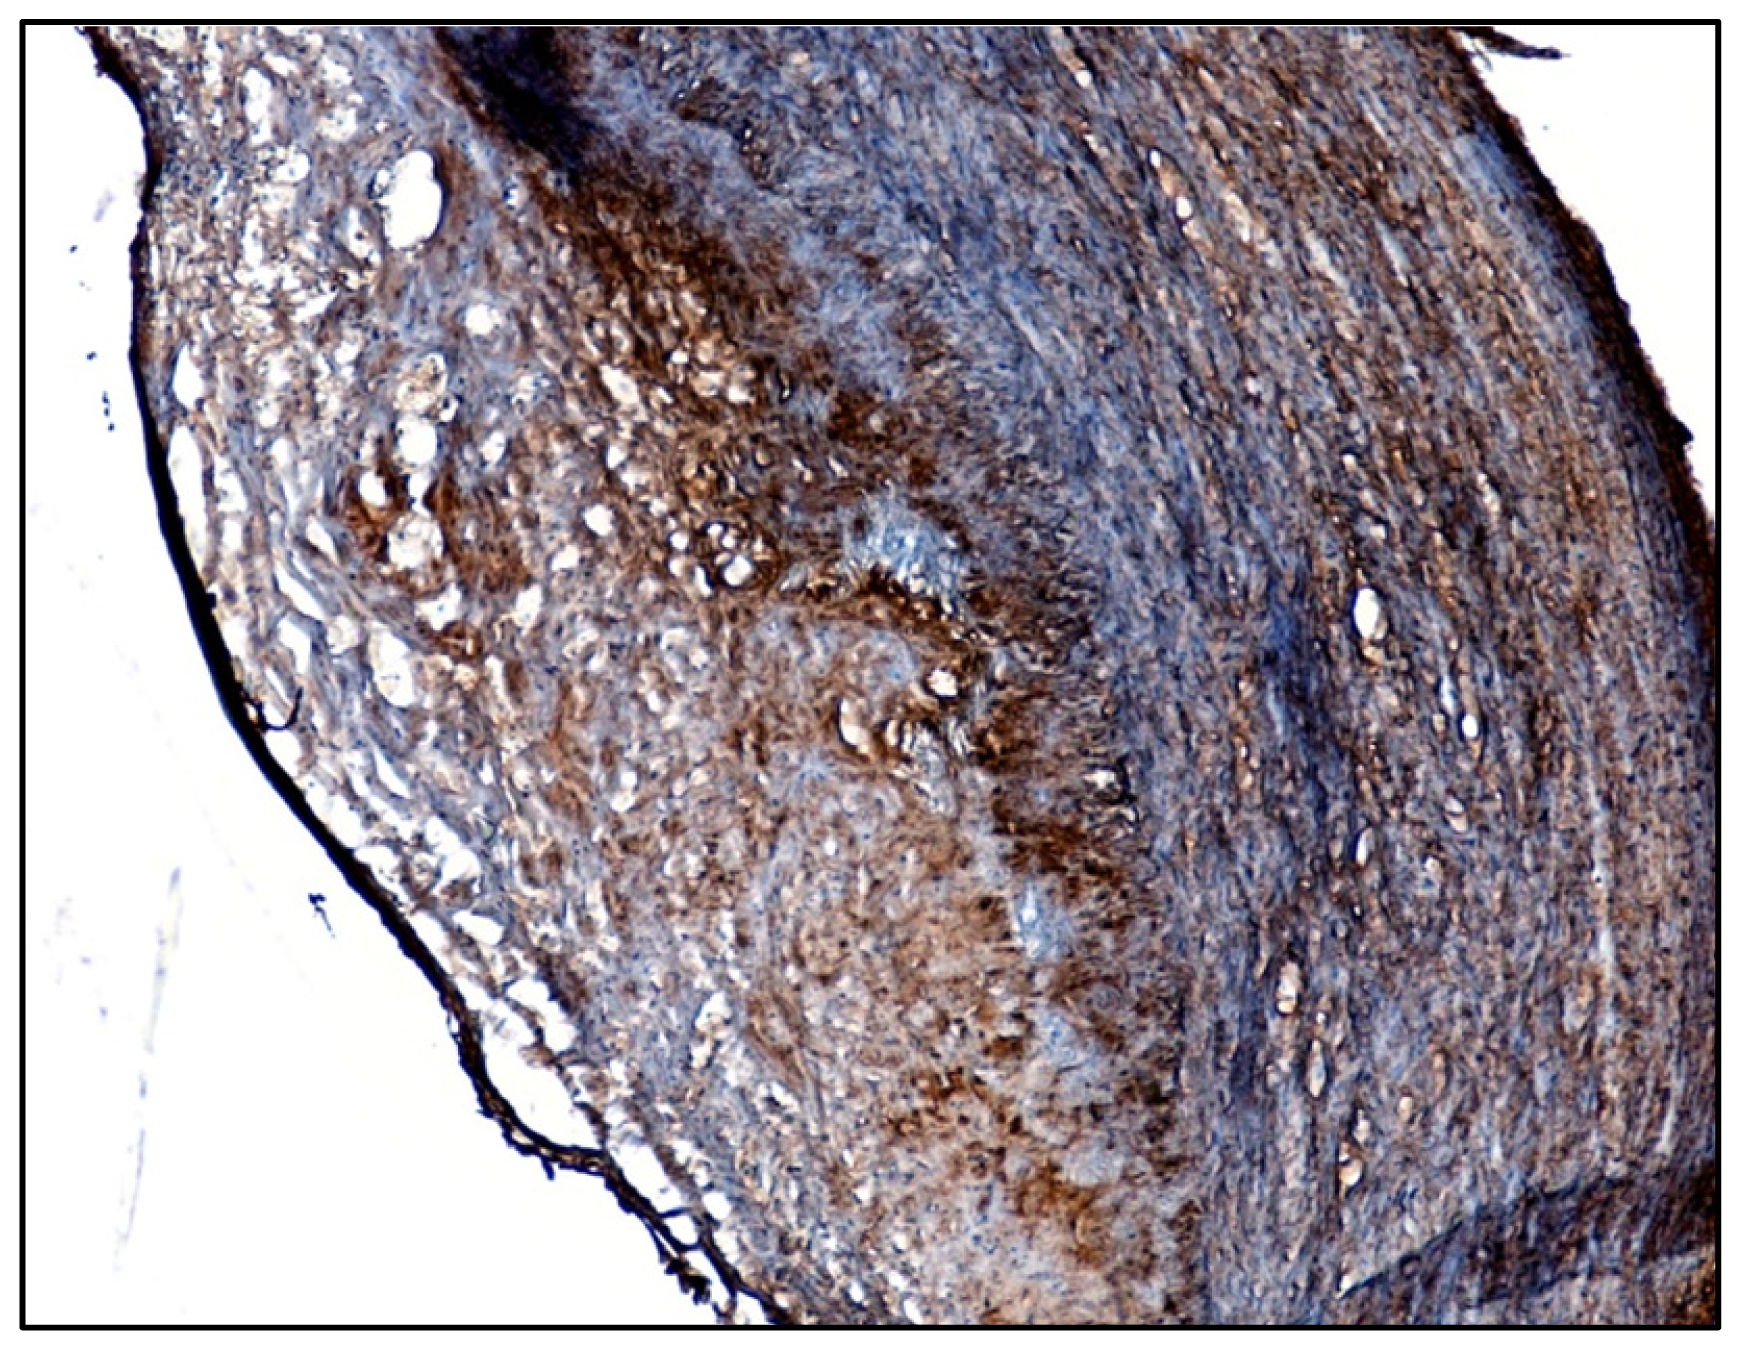

2.1. Identification of β1-Integrin in Human Atherosclerotic Plaques

3.1. Immunohistochemical Detection of β1-Integrin in Human Carotid Plaques